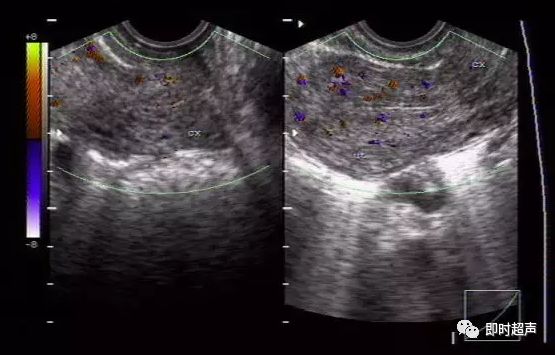

正常子宫及宫颈血流图

2.疑宫外孕时顺着子宫两侧的丰富的索状动脉血流(输卵管所在)去寻找,又快又准。